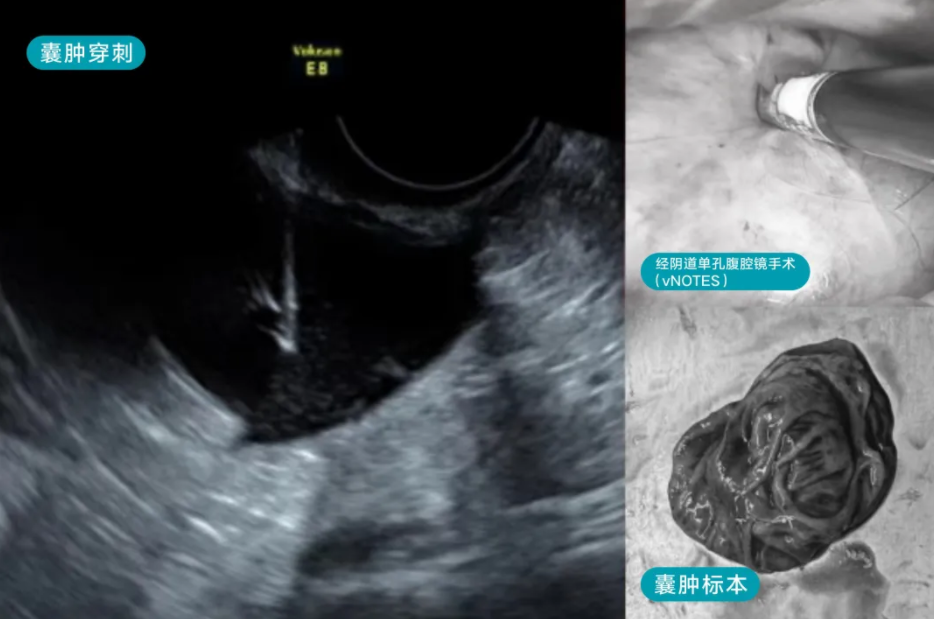

27岁的李女士,5年前发现卵巢囊肿,囊肿达5cm,考虑卵巢巧克力囊肿可能性大,外院给予口服地诺孕素治疗。龚晓明在术前充分评估了病情,虽初步考虑巧克力样囊肿可能性大,但仍保持谨慎态度,不排除单纯性卵巢囊肿的可能性。最后龚晓明教授团队给这位女士采取了日间手术,穿刺液是清亮液体,行卵巢囊肿无水酒精固化治疗,囊内液送病检查找瘤细胞。

卵巢囊肿是一种常见的妇科病,分为生理性囊肿和病理性囊肿,生理性囊肿不需要治疗,病理性的囊肿一般情况下需要腹腔镜手术治疗,但通过卵巢囊肿抽吸+硬化治疗的方式,可以不开刀穿刺治疗卵巢囊肿,创伤小,预后好,且穿刺后能阻止囊肿内皮细胞的分泌功能,促进囊腔闭合,降低复发率,目前已成为治疗卵巢囊肿的首选方法。也是目前创伤最小的治疗方式,几乎没有伤疤和出血,术后不影响正常的工作和生活,一般无需住院,日间手术即可完成(麻醉恢复以后即可出院)。